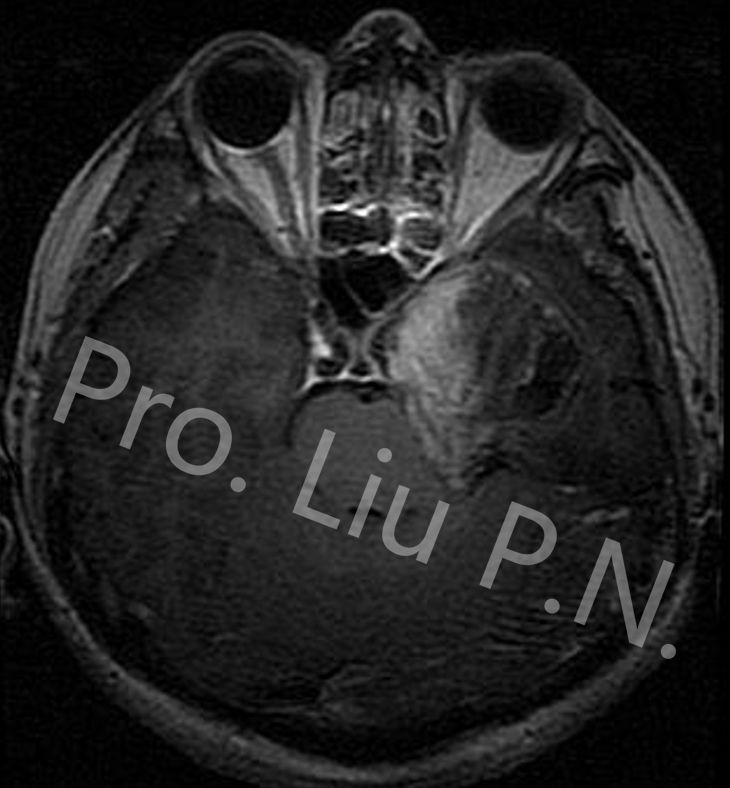

十、经筛-翼突入路手术案例

--左海绵窦神经鞘瘤

![]()